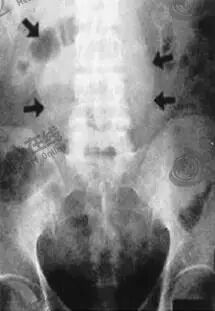

(1)腹部X线

腹主动脉瘤行腹部X线检查时,瘤壁呈蛋壳样钙化,部分可见瘤体轮廓(如下图);当X线检查呈阴性时不能排除诊断。